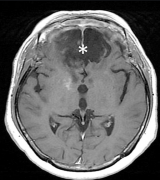

脑膜瘤3cm-4cm严重吗?脑膜瘤不开刀能活多久? 脑膜瘤(Meningiomas)是一种长在脑膜及脑膜间隙的的肿瘤,在颅内常见,80%以上脑膜瘤都是良性的肿瘤。典型的脑...

脑膜瘤 是脑膜的肿瘤,脑膜是覆盖大脑和脊髓的膜。较常见的是良性脑膜瘤或I级脑膜瘤,它们很小,不会像癌性肿瘤一样无限期地生长。非典型脑膜瘤w...

脑膜瘤 是发生在脑膜上的脑瘤,脑膜是包围和保护大脑和脊髓的组织(图1)。尽管大多数脑膜瘤不是癌性的,但当它们生长并压迫大脑或脊髓的重要部位时,...